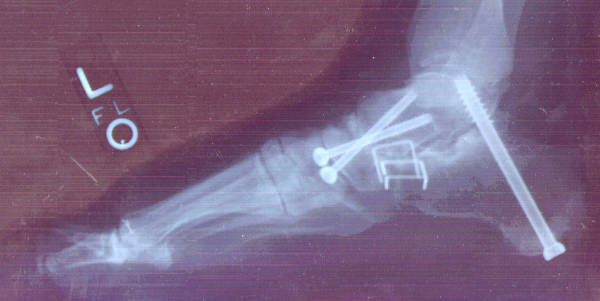

Since the posterior tibialis forms the arch of the foot, it was necessary to replace its function with a permanent arch formed by various bones of the foot. July 28, 1999 Dr. Cooper operated, using titanium screws and staples to hold three joints – the subtalar, calcaneocuboid, and talonavicular – in position until the bones became permanently fused. To make sure the bones fused properly, he also removed some bone from the tibia, just below the knee – necessitating another incision – ground it, and packed it between the four bones involved: the talus, calcaneus, cuboid, and navicular.

Six weeks later the cast was removed (stitches were removed after two weeks, through "windows" that were left in the cast) so the foot could be X-rayed in a natural position to determine that healing was progressing as desired.

Originally Dr. Cooper had said that he might remove the heel screw because it came so close to the anklebone, but he later determined that it was best to remove all the screws because they could tend to migrate

The removal, in March 2000, was an outpatient procedure and after a week she got the stitches removed. The screw holes, which can still be faintly seen, would fill in within a few weeks. The staples, however, remain, of interest to airport metal detectors.

When I told Dr. Cooper that I was going to put a photo of the screws on the Internet, he suggested that I should auction them off on eBay!